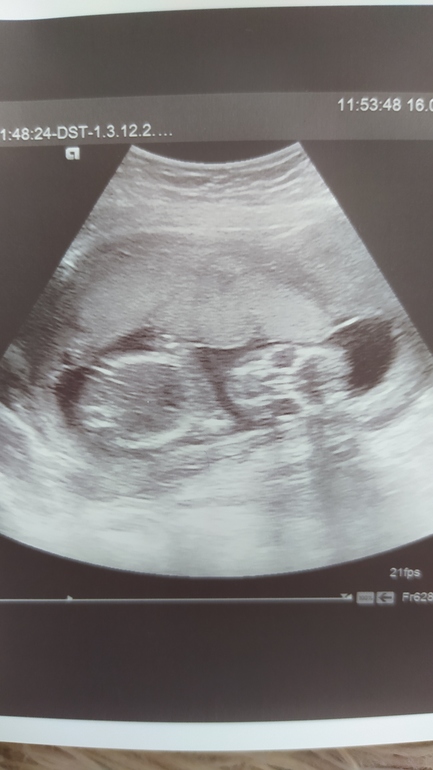

Фото прикрепляю с 13 и 17 недели ( может кто увидит пипиську?🤭)

17 недельЮлия Х